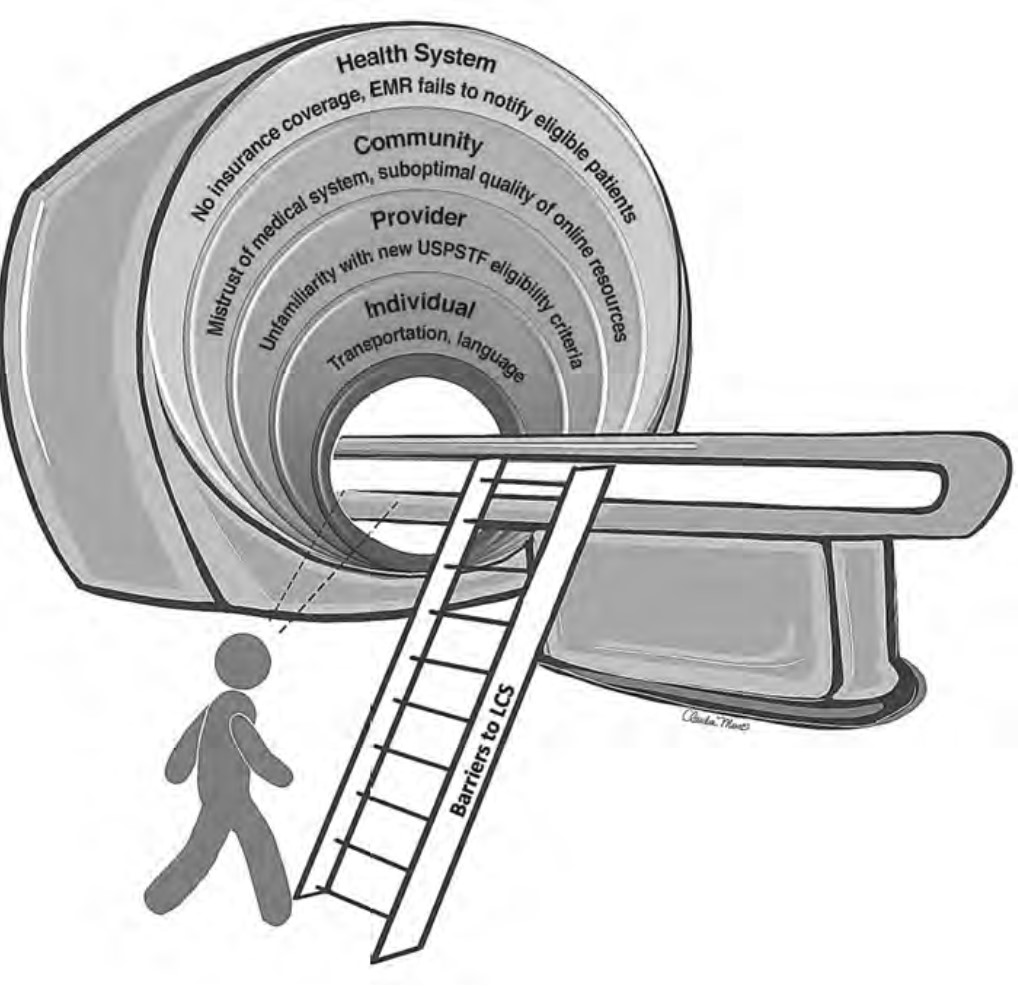

The recent update in the U.S. Preventive Services Task Force (USPSTF) LCS eligibility guidelines lowers the required smoking history to 20 pack-years and age to 50 years [7]. This provides an opportunity to improve overall LCS participation rates among diverse patient populations through tailored approaches that consider barriers related to social determinants of health. Therefore, it is vital that we take steps to understand barriers to LCS and develop targeted multilevel outreach interventions to increase LCS participation rates. The purpose of this InPractice piece is to use a modified social-ecologic model of barriers to LCS (Fig. 1) to discuss multilevel interventions and advance equity in LCS uptake among diverse patient populations by increasing awareness, opportunities, and participation in LCS (Table 1). This framework can be adapted to advance equity in LCS among radiology practices in different settings.

At the individual level, some of the barriers to awareness include unfamiliarity with LCS as a health preventive service tool (Fig. 2), unawareness of the new USPSTF and Centers for Medicare & Medicaid Services (CMS) recommendations for LCS, unfamiliarity with insurance coverage and costs, uncertainty about available accredited LCS programs, lack of culturally appropriate information, and lack of information at an appropriate health literacy level [8–10].

At the provider level, unfamiliarity with the new USPSTF and CMS recommendations and identifying patients who are eligible under the new guidelines for LCS are substantial barriers reported in the literature [9–11]. Other barriers at the provider level include unfamiliarity regarding where to refer patients; unfamiliarity with insurance coverage; lack of knowledge about available resources for management of abnormal LCS findings and follow-up of incidental findings; and skepticism about the benefits of LCS, given that clinical trials recruited predominantly White non-Hispanic patients with a higher socioeconomic status than that of the general U.S. population [10].

At the community and health care system level, suboptimal quality of institutional information about LCS (i.e., information not tailored for the surrounding communities) and a lack of institutional social media presence or engagement through social media campaigns to disseminate information about LCS are barriers to LCS [12, 13]. Furthermore, electronic medical records (EMRs) that are not optimized to automatically notify providers of eligible patients have been reported as a barrier [10].